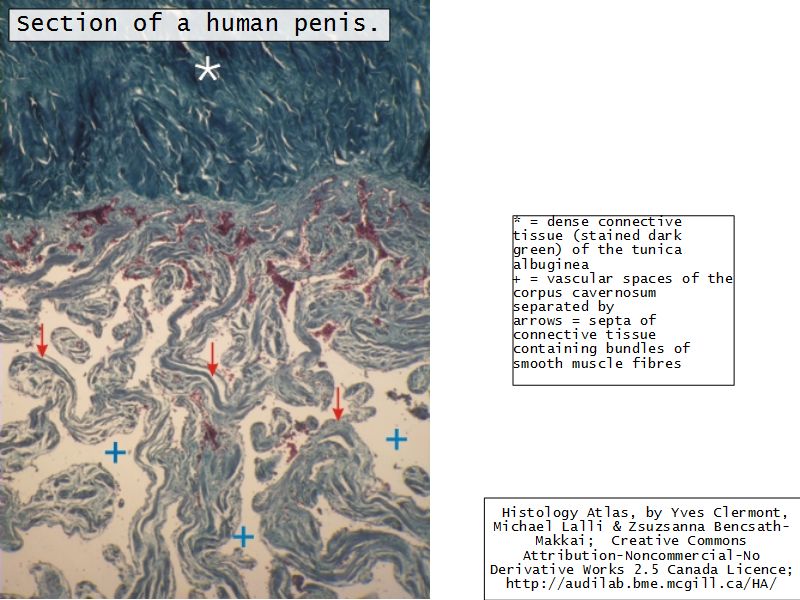

Penis

Slide 83Penis

- 3 cylindrical masses erectile tissue

- 2x corpora cavernosa

- 1x corpus spongiosum

- Surrounded by tunica albuginea

- Covered by skin

- Traversed by urethra

Tunica albuginea

- Fibrous connective tissue sheath

- Surround erectile bodies

- Dense collagen bundles

Corpora cavernosa

- Paired erectile bodies

- Irregular vascular spaces

- Lined with endothelium

- Trabeculae CT

- Smooth muscle cells

Corpus spongiosum

- Erectile body surrounding urethra

- More elastic fibres

- Few smooth muscle cells

- Vascular spaces uniform